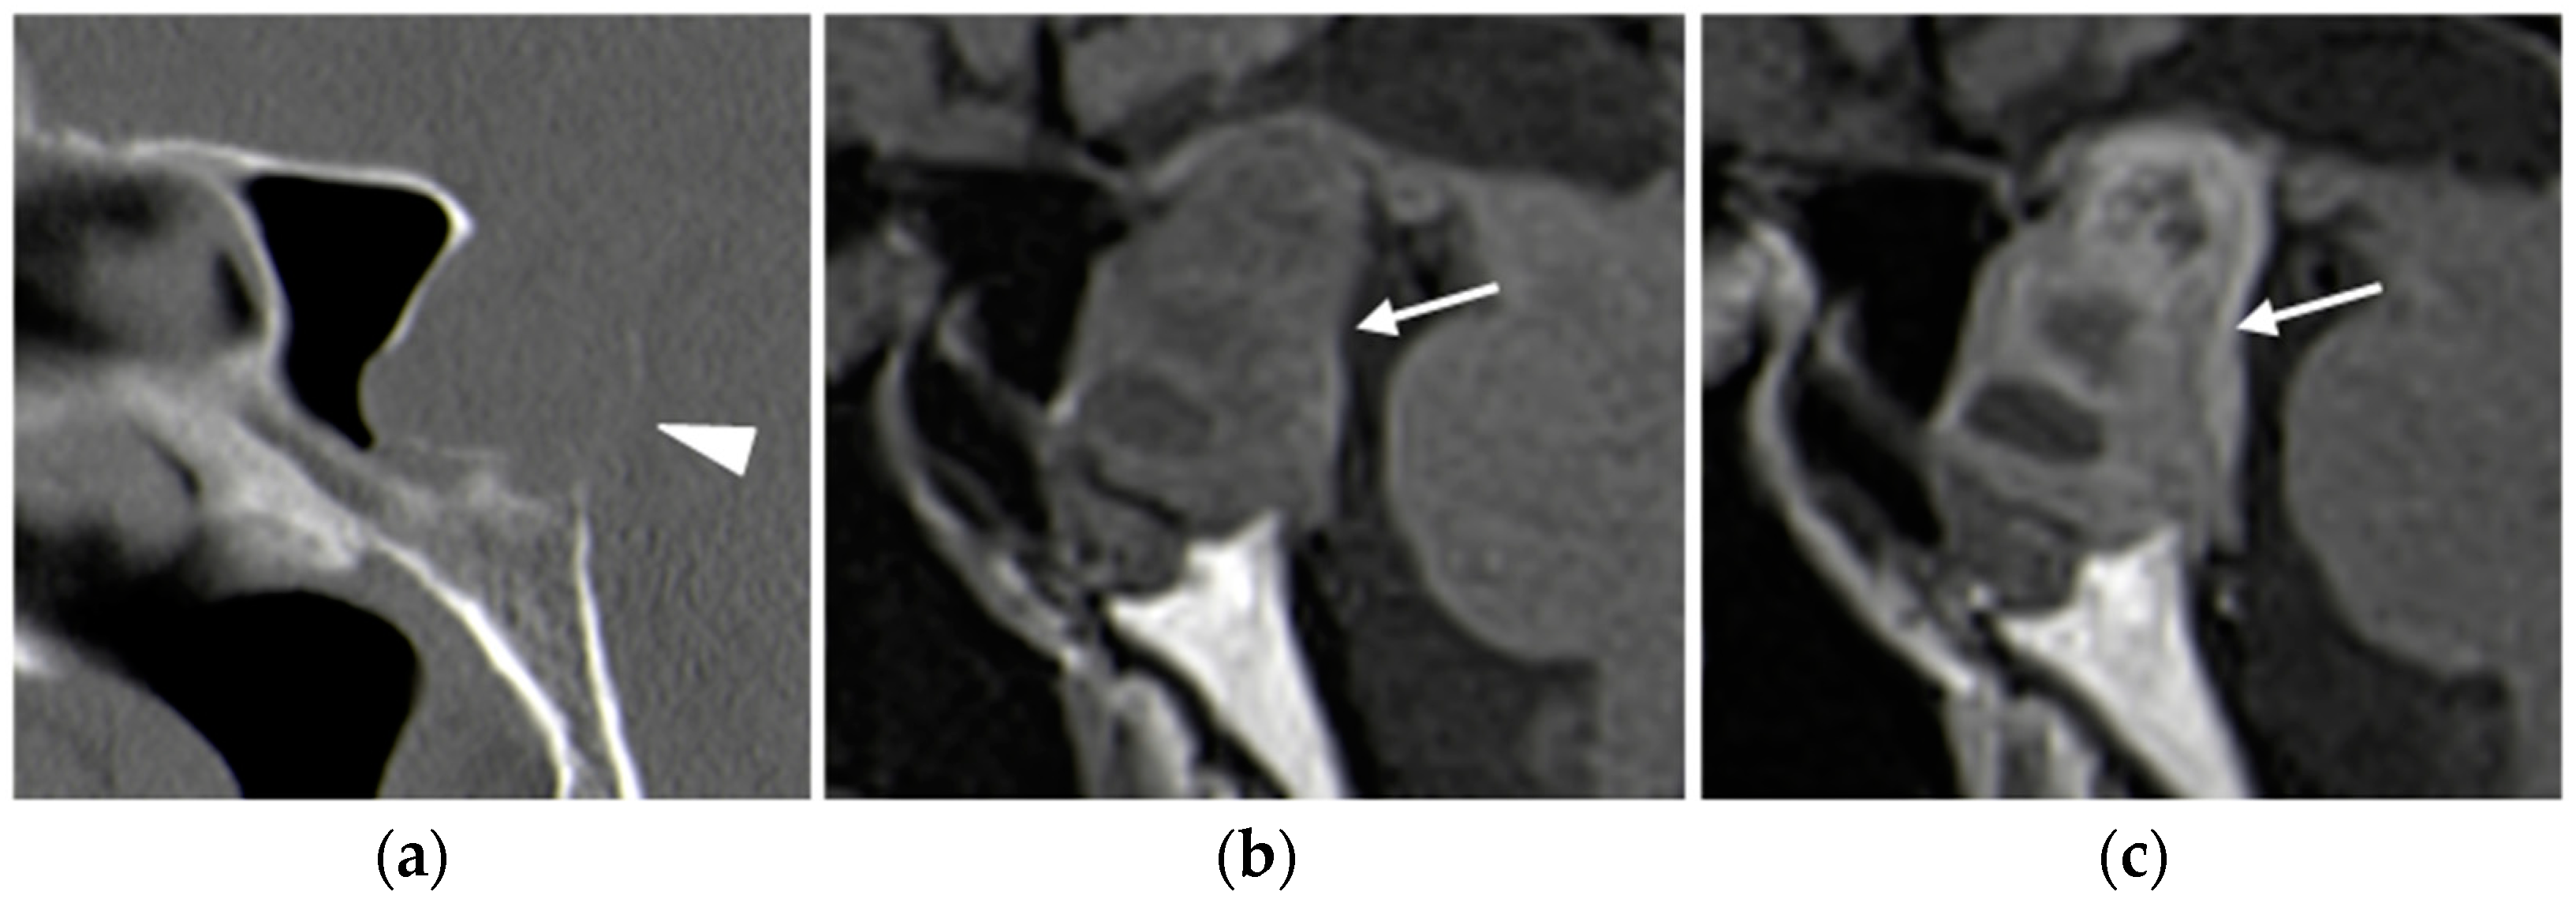

CT

MRI

| Pituitary adenoma | No role | Only if MRI is absolutely contraindicated. | Almost isointense on T1/T2. DCE post-contrast | No role | No role |